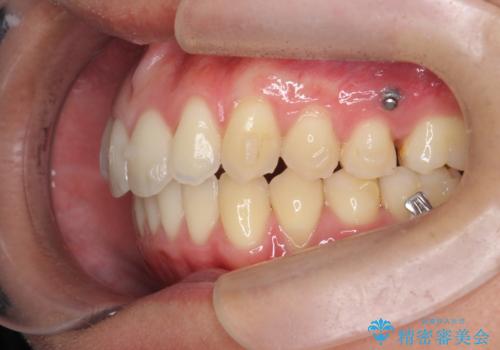

過蓋咬合・上顎前突・叢生を改善するマウスピース矯正

以上のような問題点をマウスピース矯正インビザラインとマイクロインプラントを用いて矯正治療を行い改善して行きます。

20時間以上のマウスピース装着、ゴムかけを遵守していただいたおかげでしっかりと噛み合わせ、がたつきの改善を行うことができました。